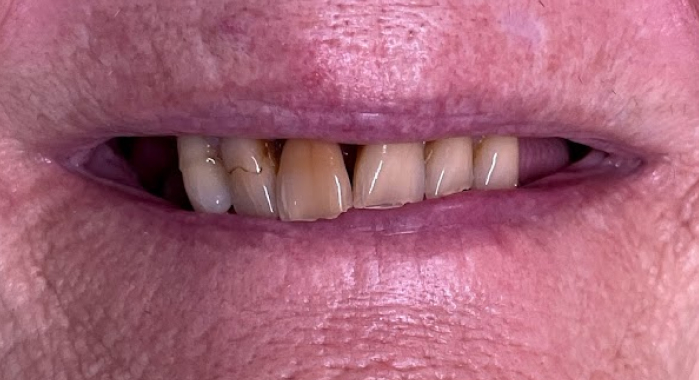

David - Two front veneers and lower fixed arch

Before